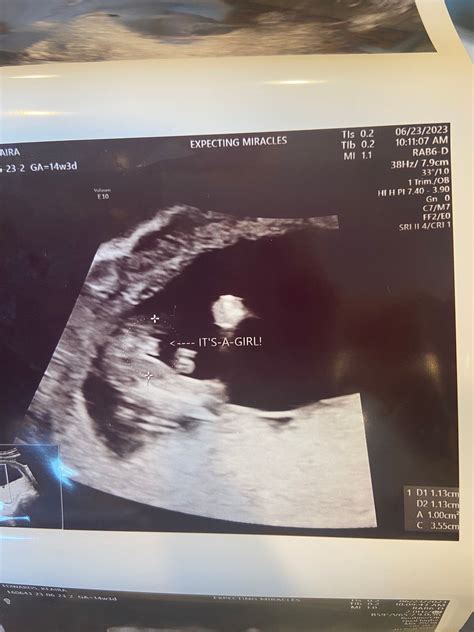

• Nuchal Translucency: The thickness of the fluid behind the baby’s neck will be measured.

The results of a 14 week ultrasound can provide important information about your baby’s health. The nuchal translucency measurement, combined with maternal age and other factors, is used to calculate the risk of chromosomal abnormalities. It’s important to note that this scan is a screening tool and not a diagnostic test. If the results indicate a higher risk, further testing, such as amniocentesis or chorionic villus sampling (CVS), may be recommended.

Nuchal Translucency This measurement helps assess the risk of chromosomal abnormalities. A thicker measurement may indicate a higher risk.